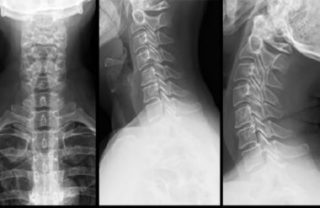

Если боль не проходит в течение 3-4 дней, необходимо сделать рентген грудного и шейного отделов позвоночника.

- Рентгенологическое исследование при подозрении на артрит, спондилолистез или нарушения осанки.